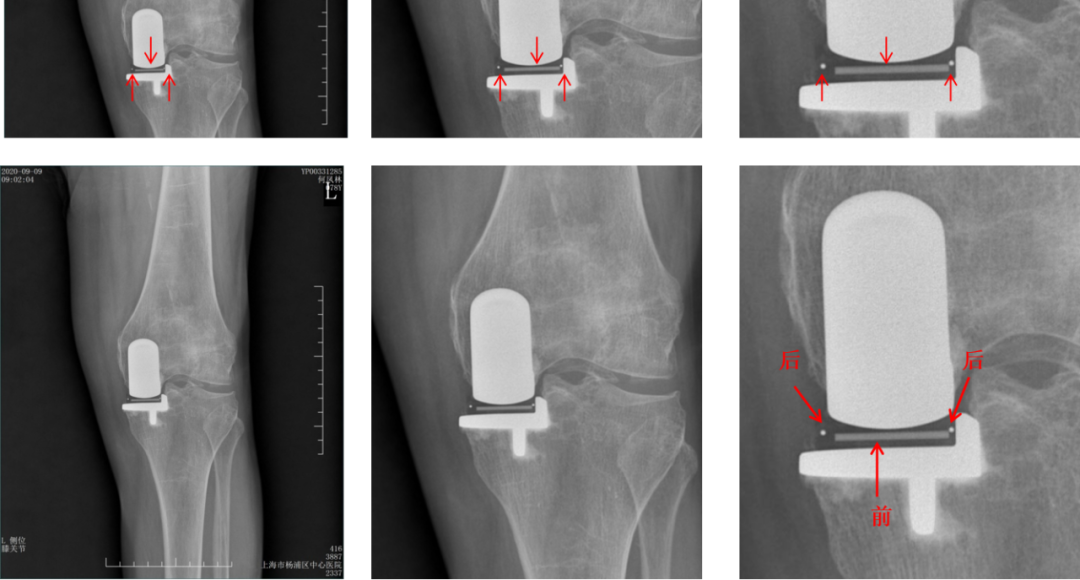

Bearing脱位在正位片上显示股骨与胫骨假体关节面接触,侧位片显示bearing位于关节囊前方或者后方。

病例3:Bearing 陈旧性前脱位2年

病例3:Bearing 陈旧性前脱位的处理